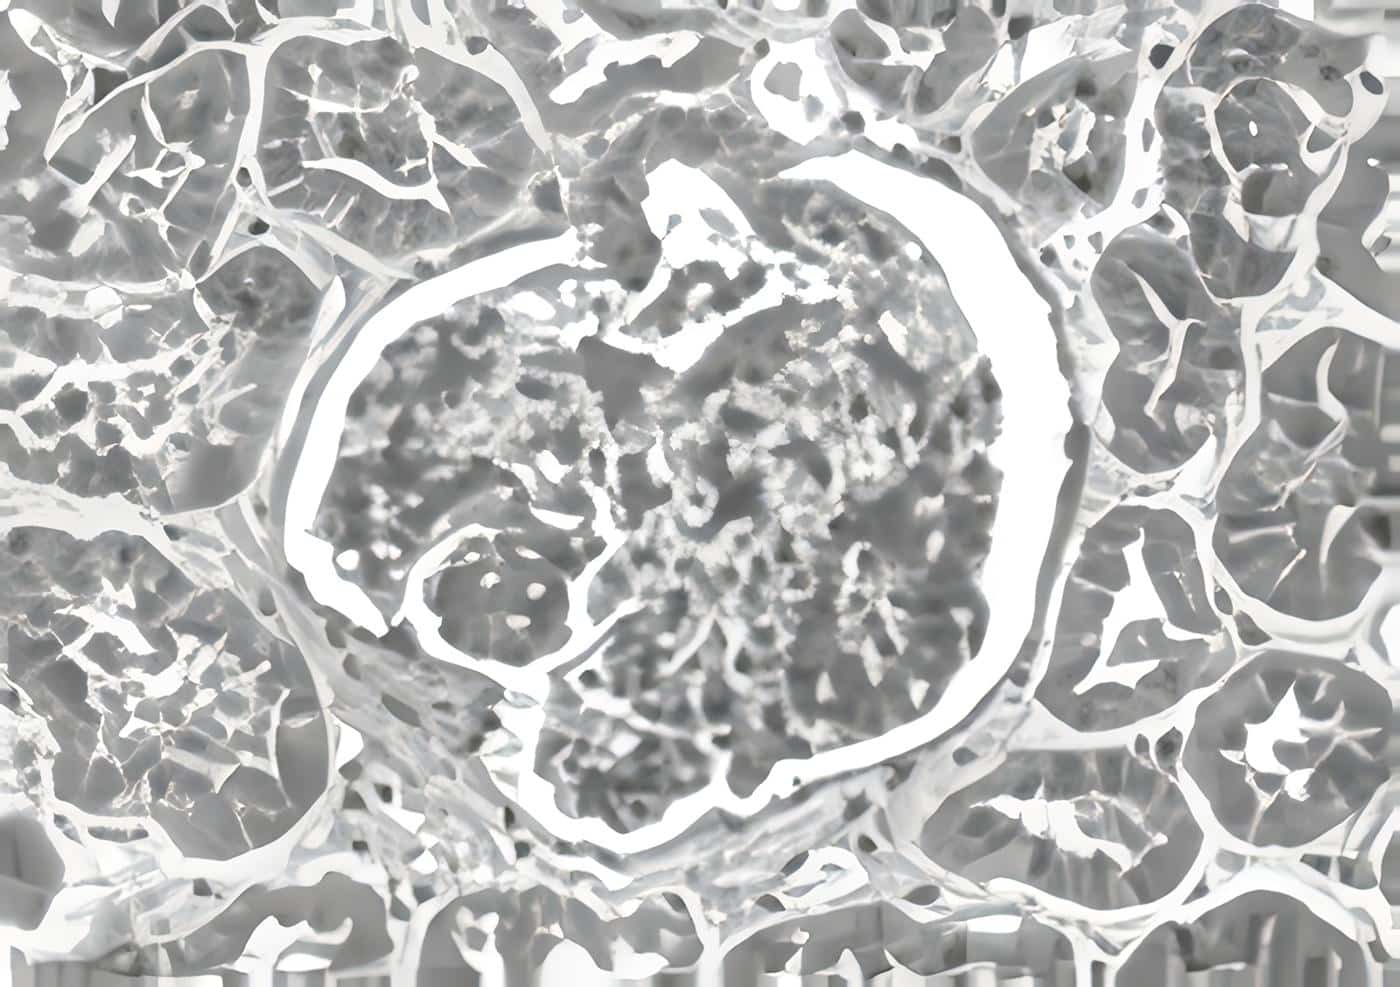

Ecografia renal: riñón derecho disminuido de tamaño, con dilatación ureteral sin hidronefrosis. Gamagrafía con DMSA: riñón derecho hipotrófico, con un área de retracción en el tercio medio y un aporte diferencial del 7%, riñón izquierdo normal con aporte del 93%. Cistouretrografía miccional: reflujo vesicoureteral grado III izquierdo.

Se realizó nefrectomía derecha, cuya descripción histopatológica confirmó el diagnostico de displasia-hipoplasia renal.

La hipoplasia-displasia renal es una patología que hoy se denomina con el término de disgenesia renal, poco frecuente y que se confunde con pielonefritis y reflujo vesicoureteral en lactantes menores, siendo una nefropatía embrionaria fetal. El diagnóstico se hace por estudio histopatológico.